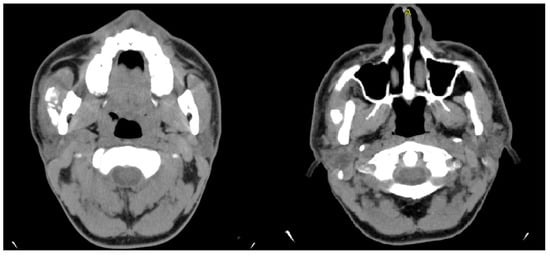

- Case 1

| 1 | Male | 48 | Osteoma of the coronoid process |

OPG CT | 19 mm | Coronoidectomy | 39 mm |